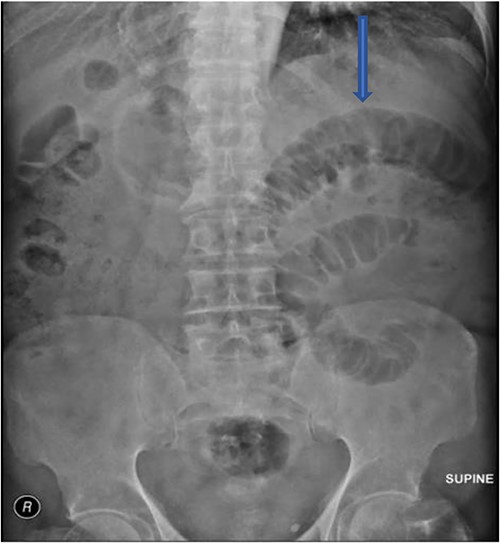

The plain film of the abdomen showed multiple air-fluid levels on the erect film (Fig. 1) and small bowel dilatation on the supine (Fig. 2). The CT showed multiple air pockets in the biliary tree, representing pneumobilia (Fig. 3). It also showed evidence of a circular radio-dense stone measuring 2 cm within the distal jejunum, leading to obstruction and dilatation of the proximal jejunum (Fig. 4).

CT is the investigation of choice. Plain films can reveal dilated small bowels, confirming small bowel obstruction [8]. The presence of Rigler’s triad on the plain film, which includes pneumobilia, dilated bowel, and ectopic gallstones, is diagnostic of gallstone ileus, but this occurs only in 9%–14% of patients [7]. Most patients require surgical intervention to relieve the obstruction. Surgery includes enterotomy and removal of the stone (enterolithotomy) or enterolithotomy with cholecystectomy and repair of the fistula [2]. Commonly, simple enterolithotomy is favored as it carries less morbidity, with or without cholecystectomy at a later date [9]. Spontaneous fistula closure occurs in up to 50% of cases [7].